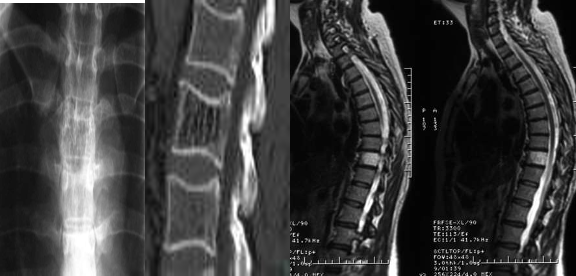

Plain film:

Findings include: sclerotic vertebra with prominent trabecular pattern, and vertical trabeculae.

CT:

Usually as an incidental finding. Better visualization of thickened vertical trabeculation.

MRI:

Signal intensity is somewhat variable, depending largely on the amount of fat content.

- T1: high is more common (fat rich).

- T2: high.